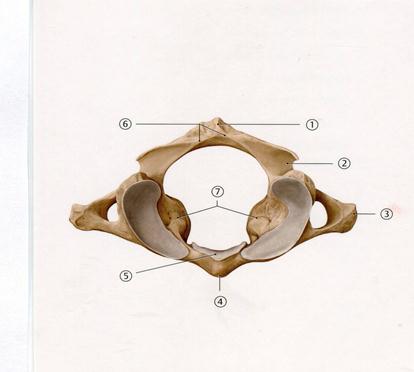

43. Төменде көрсетілген суреттегі белгіленген №7венаны атаңыз.

D. Жартылай сыңар

44. Төменде көрсетілген суреттегі белгіленген № 4 анатомиялық құрылымды атаңыз.